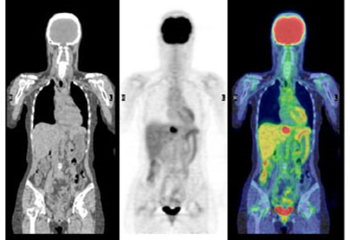

IV.4.7.3. PET–CT